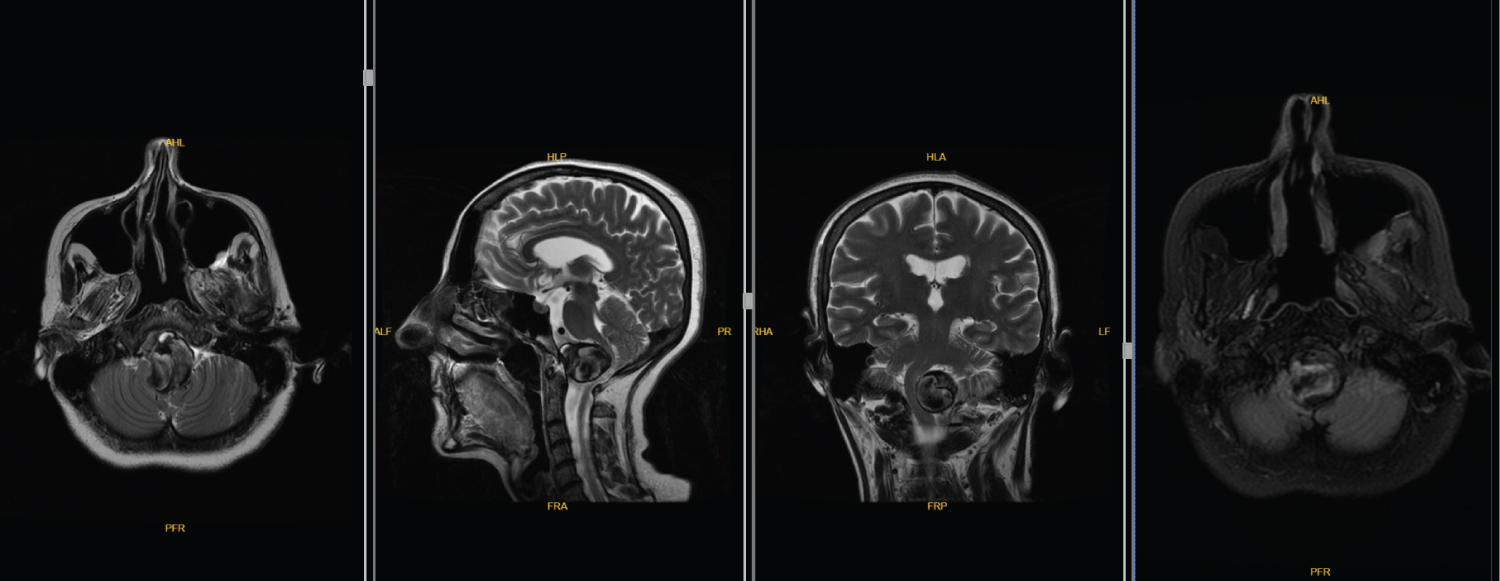

After 2 months of the operation, the patient had increased white phlegm and her choking cough was continuing. Furthermore, the patient's right limb muscle strength was improved compared with that pre embolization and the patient has Medical Research Council grade 5 muscle strength in the right limb. Three months after embolization, re examination of the head MRI and MRA revealed that the aneurysm was completely occluded [Raymond Roy classification, Class I [7]]; although, the brainstem was still compressed when comparing with the pre-embolization Mri (Figure 3). At 12 months after surgery, her phlegm was markedly improved and discontinued with the medical drugs. Cough and hoarseness disappeared. Re examination of DSA revealed no aneurysm recurrence [Raymond Roy classification, Class I [7]] and no stenosis in the parent artery on MRI (Figure 4) and computer tomography angiography (Figure 5). The modified Rankin scale score [8] of the patient is 1 point.

Figure 4: No stenosis in the parent artery on MRI. View Figure 4

Figure 5: Computer tomography angiography. View Figure 5